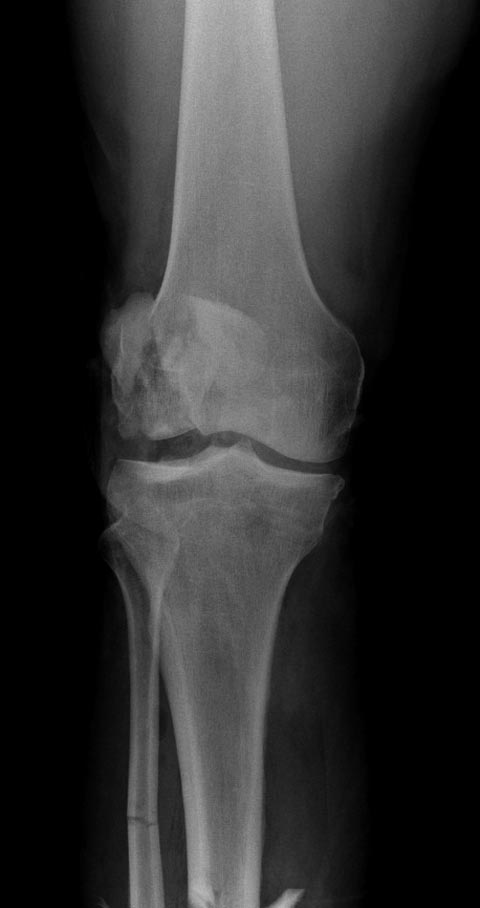

Re: Патологический перелом мыщелка бедра

Посты: “Патологический перелом мыщелка бедра” и “Опухоль дистального метаэпифиза бедренной кости” идентичны, и это картина одного того заболевания, только в различных стадиях. Окончательный диагноз любого опухолевого процесса ставится на основании биопсии, а предварительный диагноз можно установить на основании рентгенологических данных.

В возрасте между 20-40 годами из доброкачественных опухолей встречаются гигантоклеточные и энхондромы, а из злокачественных - только хондросаркома! Интенсивность и характер боли также имеет значение, например, усиление боли означает быстро растущую остеобластому, ГКТ или малигнизацию. Стрессовые и патологические переломы могут встречаться при злокачественном и при доброкачественном опухолях. Разрыв или вовлечение кортикального слоя означает метастазирование или стрессовый перелом. Четкие контуры показывает неагрессивную форму.

На основании этих данных можно предположить, что здесь имеем ГКТ дистального бедра. Первый случай, оперировать можно в обычном ортопедическом отделении. Доступ латеральный, удалить содержимое и заполнить цементом. Цитотоксичний эффект создается за счет температуры при твердении цемента. И опухоли с вовлечением в процесс более чем 40% нуждаются в дополнительной фиксации, иначе после удаления опухоли может пострадать стабильность. Любая латеральная пластина подойдет для этой цели.

Второй случай, коллапс латерального мыщелка за счет стрессового перелома. До операции надо уточнить диагноз биопсией и определить границу поражения на КТ и МРТ. Здесь имеется вовлечение кортикального слоя и вряд ли дистракционный метод поможет восстановить контур мыщелка. Онкологический вариант замещения с удалением неплохой вариант, но агрессивный. Возраст молодой и при наличии костного банка можно было восстановить аллографтом. Сегодняшняя технология (3Д и КТ) позволяет подобрать идеальный размер целого мыщелка (аллографт).

Здесь представлен посттравматический дефект латерального мыщелка и лечение аллографтом.